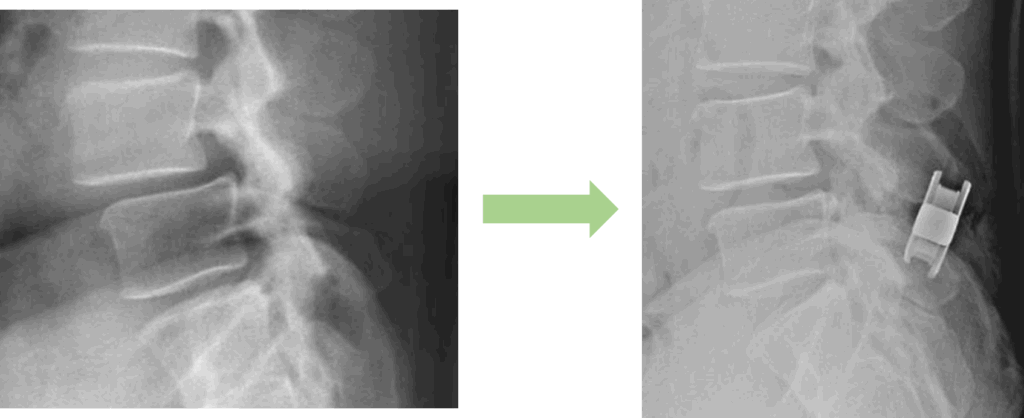

画像及び所見について

- L1/2,3/4,4/5,5/s-椎間板変性

- L4/5-脊柱管狭窄症

- L4-前方すべり

以上の事が画像上認められます。

・L4/5-脊柱管狭窄症を認め、主症状の原因の可能性がある

Qfusionを入れた画像になります。すべり・椎間板の高さが改善しているのが分かると思います。